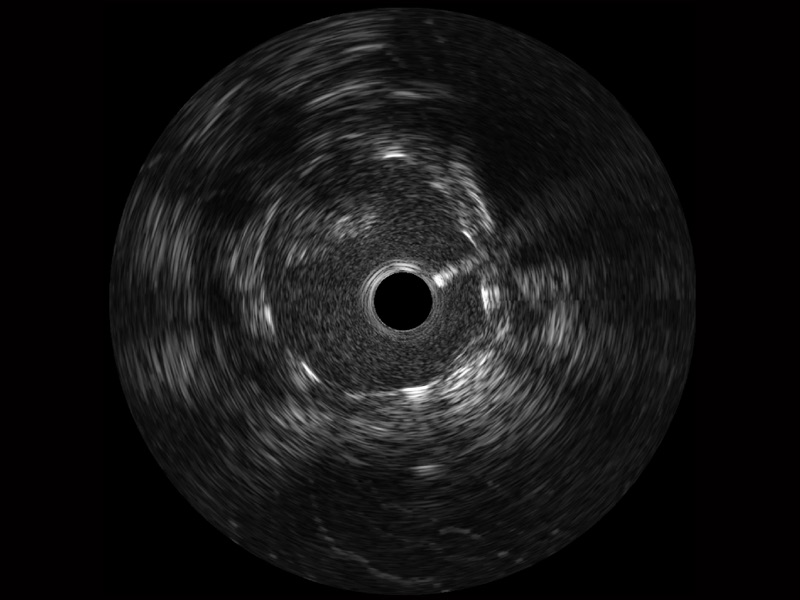

传统IVUS图像

对比传统IVUS导管成像,哈哈体育官网宽频IVUS图像的近场支架梁显影更细腻,远场中膜外血管仍清晰可辨,兼顾远中近,兼顾分辨力与穿透深度